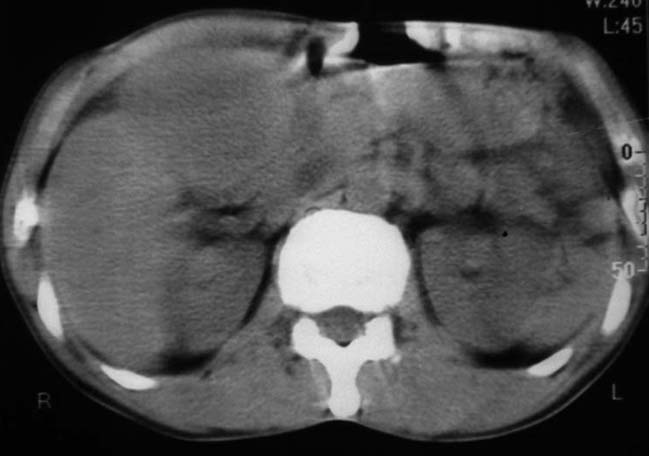

男,50y,右上腹包块痛10天,查:右上腹饱满,右肋下触及6*6cm大小包块,质硬,压痛。患者诉:10天前感冒胸闷,痛,后痛及右上腹部,既往有肝炎病史。

没有增强!只能考虑左叶内侧段巨块型肝癌(外生型)可能性大;胆囊呢?不除外胆囊癌累及肝脏。

我倒是先考虑胆囊癌(肿块型)肝脏受侵可能性大,做个c+

病变位于胆囊窝内,其内密度不均,肝总管及胆总管扩张,胃里面没有清水充盈,不解为什么楼主不做好了准备再做呢,支持:“左叶内侧段巨块型肝癌(外生型)可能性大;不除外胆囊癌累及肝脏”建议增强吧。

考虑:肝左内叶巨块型癌,主动脉旁淋巴结转移.(有一层面似见胆囊受压.)